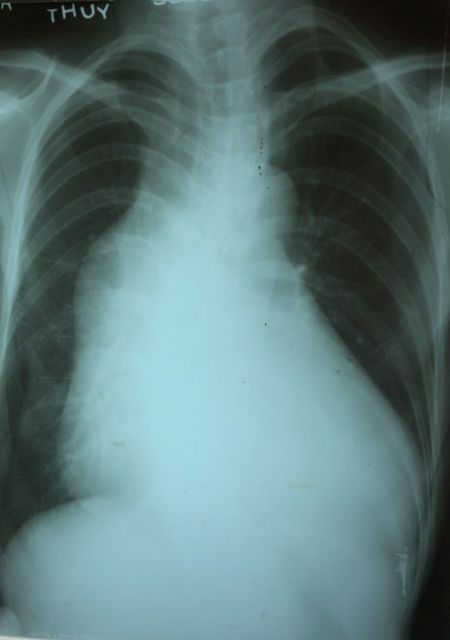

Phình động mạch chủ lên

Phim X quang lồng ngực thẳng lưu ý hình ảnh phồng động mạch chủ lên